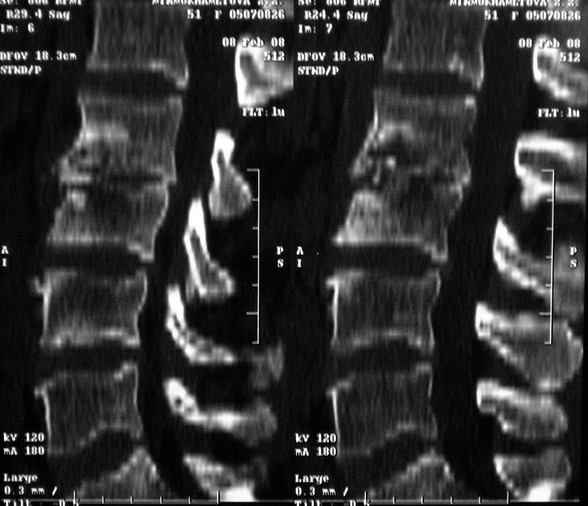

Re: Требуется телеконсультация Вертебролога

послал Коваленко А.Н. 12 Февраль 2008, 22:13

MRI через три недели